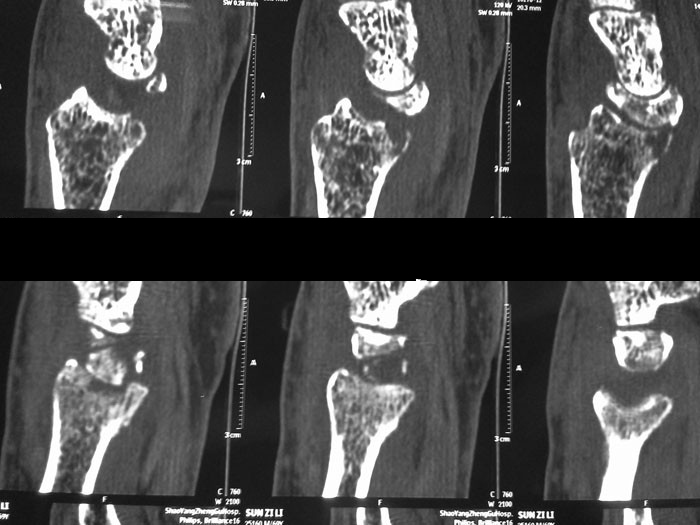

右手腕ct图片高清

右手腕ct图片高清,手腕ct图片高清

腕关节ct

手腕ct图片高清

正常手腕ct图片高清

手腕ct图片